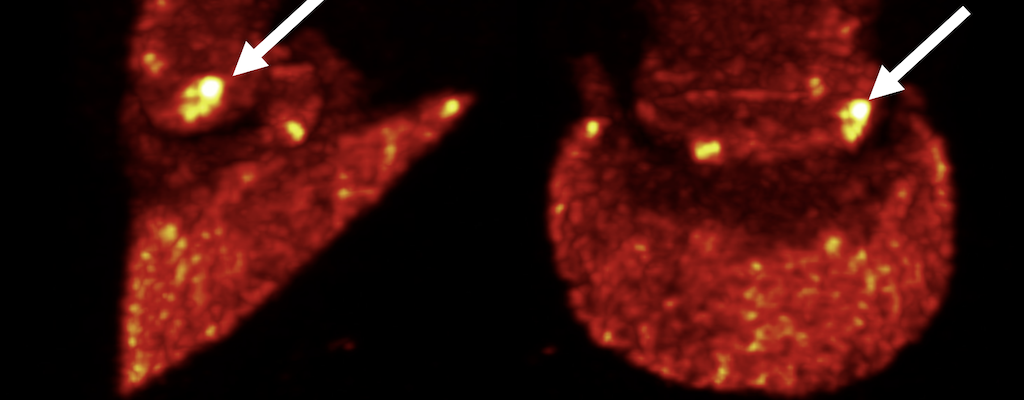

Positron Emission Tomography (PET) is a powerful molecular imaging technique commonly used in human medicine. Our mission is to deliver the full power of PET to the equine veterinarians by designing PET imaging devices meeting unique needs of this unique community.

MILE-PET® is the only PET device for imaging of limbs in standing, lightly sedated horses without anesthesia.

Molecular imaging with PET is now available in a standing sedated equine patient